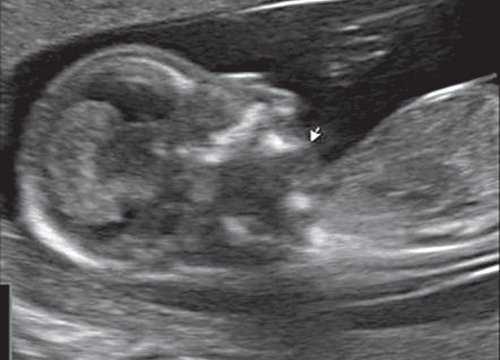

Обе ветви нижней челюсти при сроке 11-14 нед беременности выглядят гиперэхогенными, а в месте слияния имеют характерный гипоэхогенный промежуток, ультразвуковой "разрыв". Этот признак визуализируется при нормальном развитии нижней челюсти (mandibular "gap").

Такие особенности ультразвуковой анатомии связаны с этапами эмбрионального развития костей нижней челюсти, ветви которой начинают развиваться из первой жаберной дуги с 7-й недели эмбрионального развития (рис. 7), и, постепенно приближаясь друг к другу к концу I триместра (на 14-й неделе беременности), образуют синостоз в области подбородка.

Размер этого промежутка уменьшается с увеличением срока беременности. Нижнечелюстной промежуток здорового плода представлен на рисунке 8.

Рис. 8. Нижнечелюстной промежуток в 13 нед беременности при нормальном развитии нижней челюсти.

При патологии нижней челюсти (микрогнатии) в срок 11-14 нед беременности при изучении коронарного скана лица нижнечелюстной "промежуток" отсутствует, нижняя челюсть представлена единой, слившейся костной массой. Отсутствие нижнечелюстного "промежутка" (mandibular "gap") при эхографии в этот срок является маркером гипоплазии нижней челюсти (микрогнатии). Варианты отсутствия нижнечелюстного промежутка при микрогнатии при различных синдромах в срок 11-14 нед беременности представлены на рисунке 9.

Рис. 9. Отсутствие нижнечелюстного промежутка при микрогнатии, при различных синдромах нехромосомного генеза в 11-14 нед беременности.